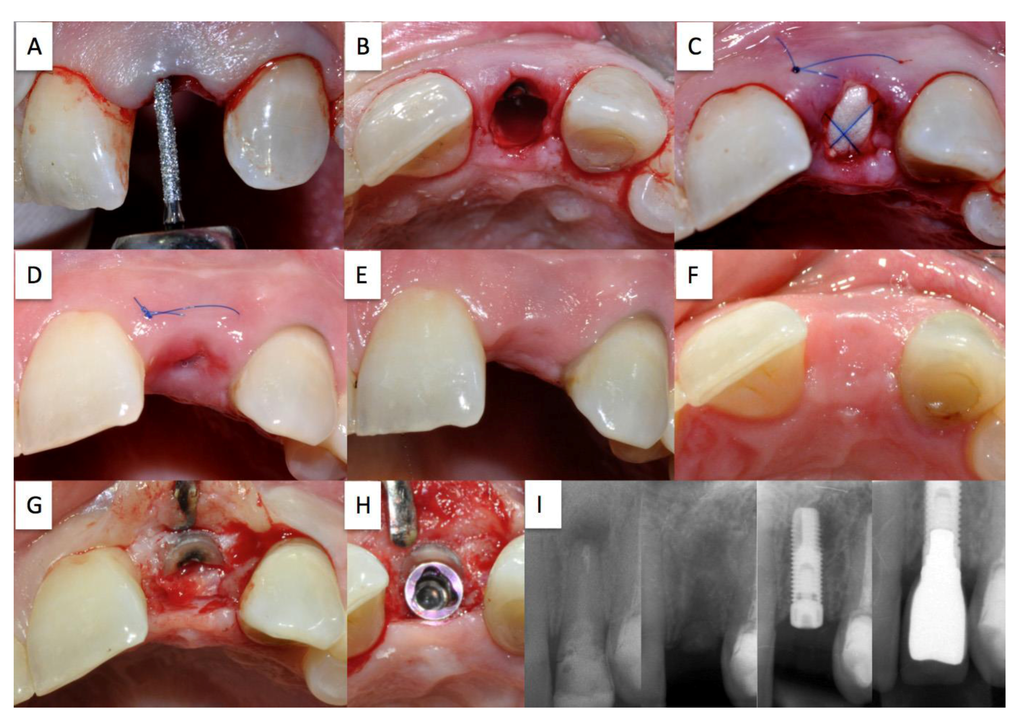

Treatment plan: Partial extraction of tooth 11 (A), prevention of alveolar ridge resorption using the socket shield technique (B,C,D), late implantation (G) of a titanium implant (Nobel Biocare Replace®). The treatment is depicted in Figure 3.

Figure 3. Case 2.

Dentistry 02 00011 g003

Chromatic aberration of the crown of the root-treated tooth 11 (A); Status post extraction with retention of the shortened and reduced root fragment (B); absorbable cone inserted into the extraction socket secured with criss-cross suture (C); healing course following suture removal after 30 days (D); completely preserved buccal bundle bone with re-entry (E); view after preparation of the implant site (F); optimum position of the implant with slight palatial shift (G); preoperative X-ray control (left), with inserted implant (middle), screwed crown (right) (H).